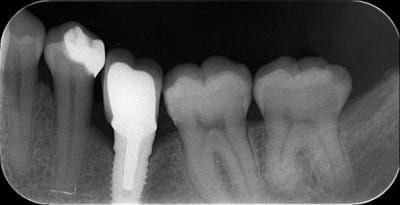

Voici trois Rx : cratère ou pas ? quel taux d'échec à 5 ans (tout les implants), ce sont les mêmes : 3I plateforme plate, deux temps chir, pas de plateform switching, pilier vissé prothèse scellée, 3 mois d'OI.

Crat 1 k8pnfh - Eugenol

Crat 2 ra8vyw - Eugenol

Crat 3 hpsffn - Eugenol